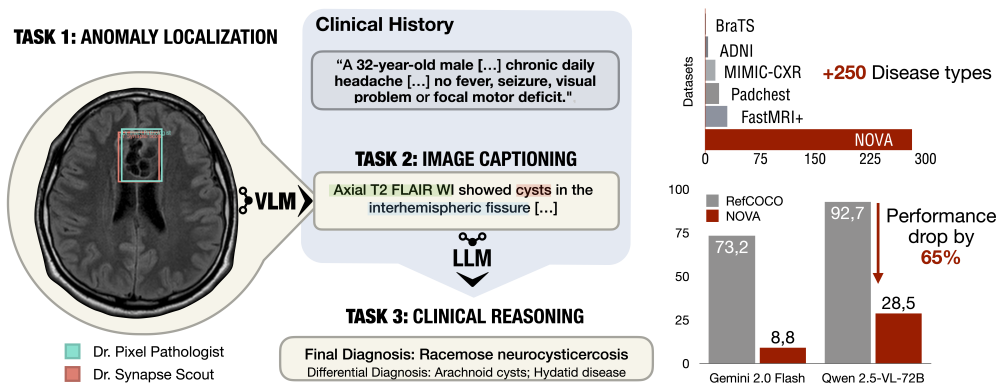

Accepted as Oral paper by NeurIPS 2025 Datasets and Benchmarks Track.

Cosmin I. Bercea, Jun Li, Philipp Raffler, Evamaria O. Riedel, Lena Schmitzer, Angela Kurz, Felix Bitzer, Paula Roßmüller, Julian Canisius, Mirjam L. Beyrle, Che Liu, Wenjia Bai, Bernhard Kainz, Julia A. Schnabel, Benedikt Wiestler.

[paper]

[huggingface]